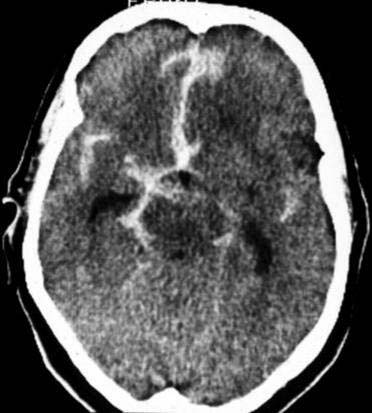

Ein 40-jähriger Patient klagt über plötzlich unerwartet auftretenden

Kopfschmerz wie noch nie.

Patient

wird zunehmend somnolenter.

CCT

nativ (d.h. ohne Kontrastmittel).

Hyperdense (60-80HE) Strukturen im

Subarachnoidalraum, hyperdense (60-80HE) Strukturen in

den Hirnfurchen und verstrichene

Gyri und Sulci.

Akute

Subarachnoidalblutung mit Blutnachweis im Bereich der Hirnbasis und der Sylvischen

Furche beidseits.

Hirnödem.

Ursache meist eine Blutung aus einem Hirnbasisaneurysma.